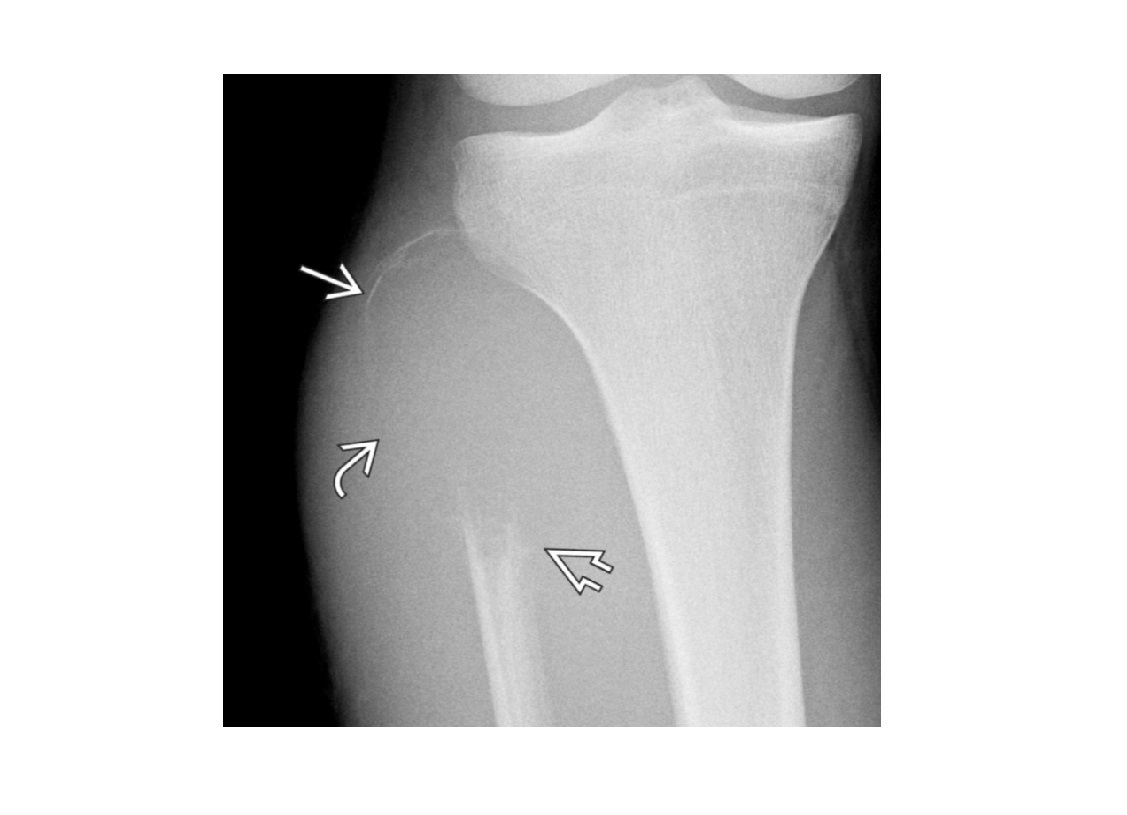

Segond fracture

Lateral tibial plateau

Associated with ACL tear (75%) and internal rotation

MR SL = Medial Reverse Lateral Segond